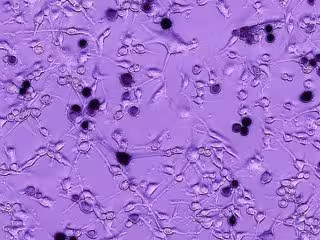

En el virus del Ébola de tipo salvaje, la MLD juega un papel en ocultar el Ébola del sistema inmune. Inyectaron este virus quimérico en los cerebros de ratones con glioblastoma, y descubrieron que la MLD ayudaba selectivamente a atacar y matar tumores cerebrales mortales de glioblastoma. El equipo trabajó con la glicoproteína MLD, no con el virus del Ébola completo.